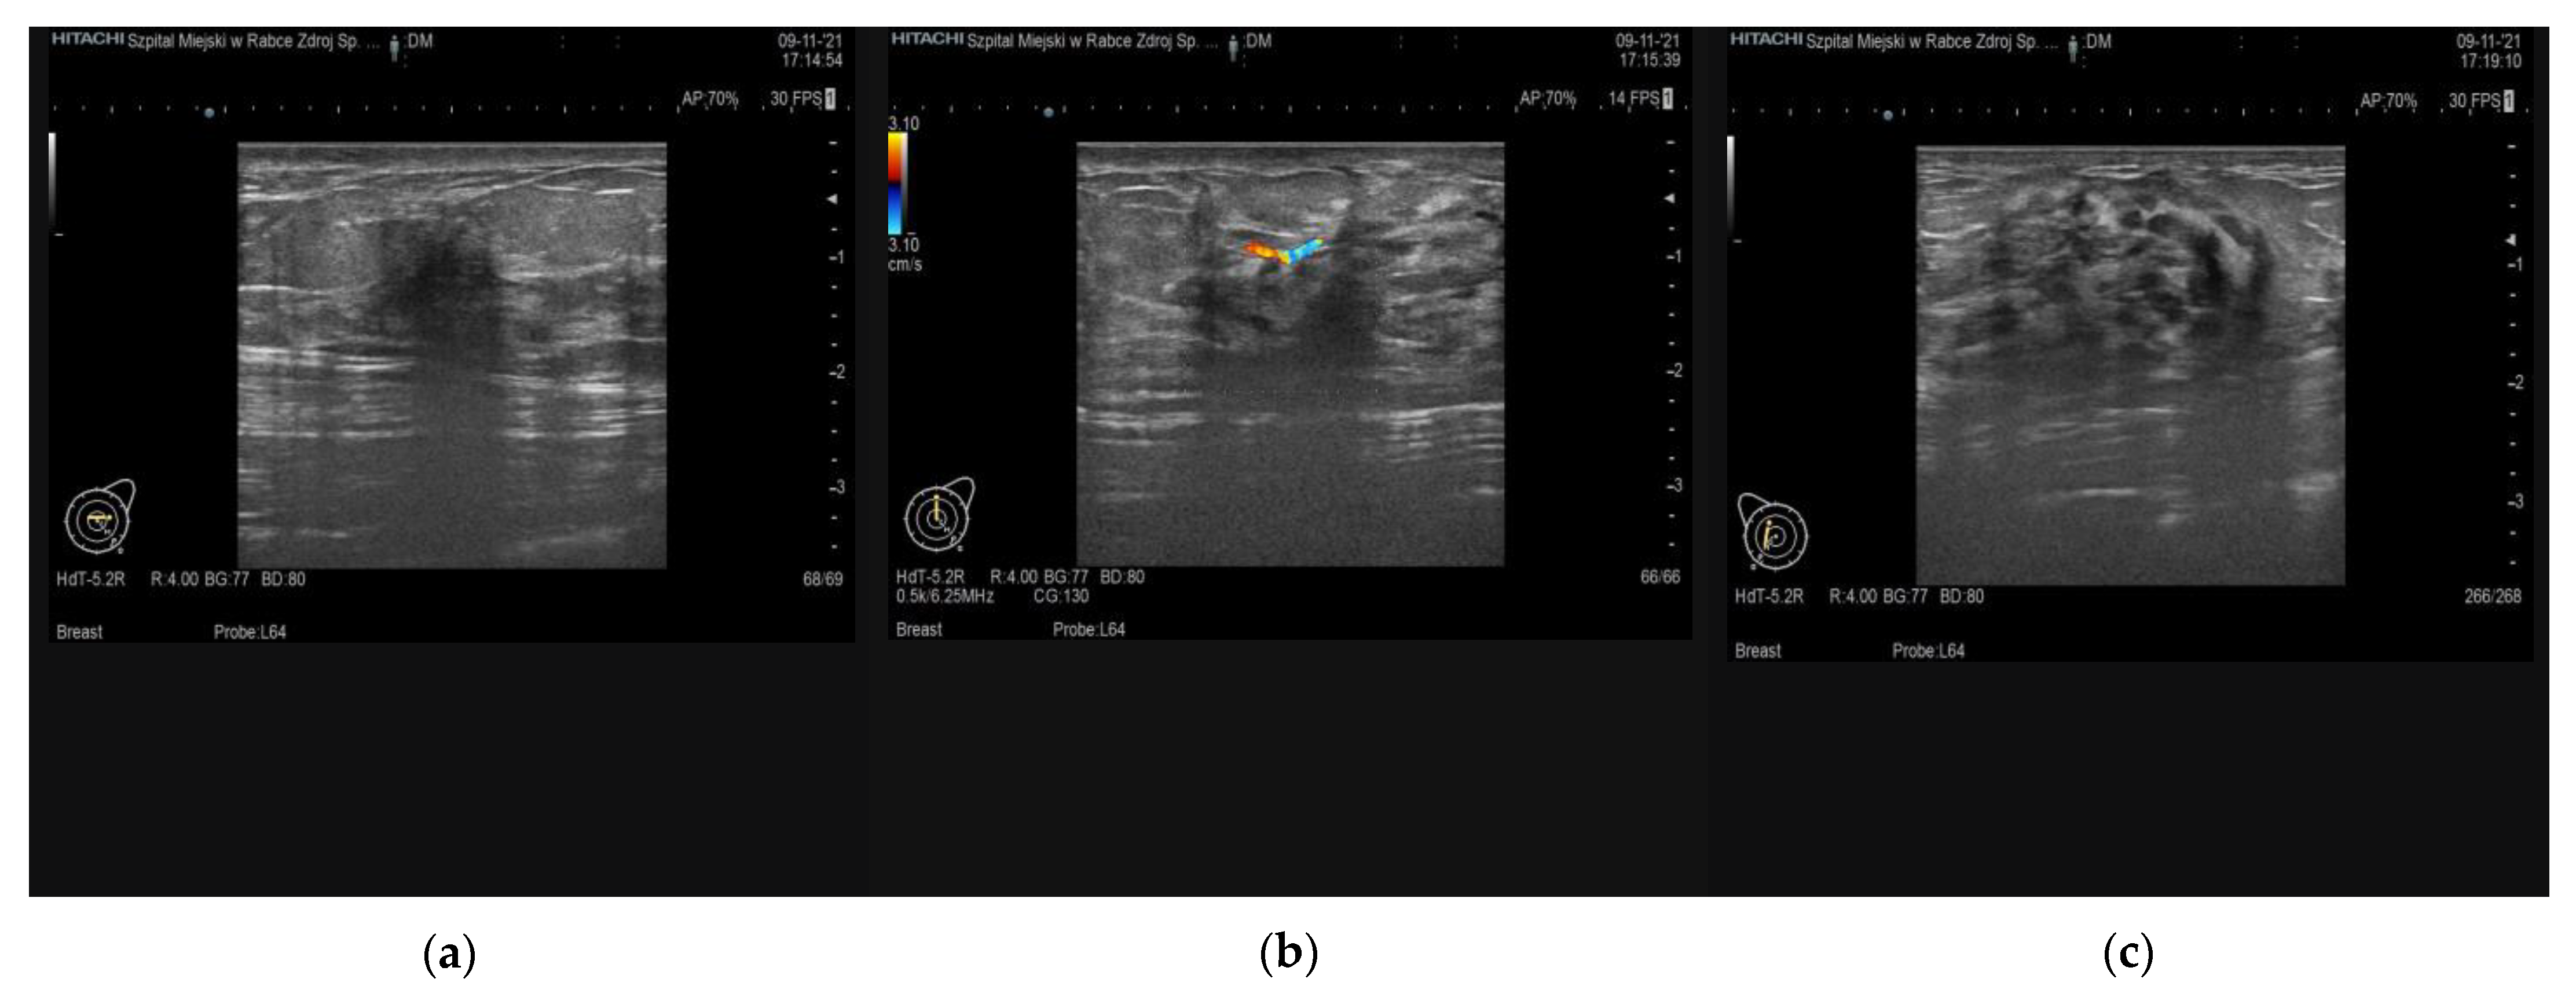

6. Imaging Findings